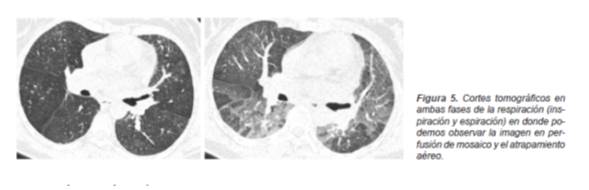

Además de los patrones específicos para el tipo de afección intersticial, contamos con las imágenes que identifican a las alteraciones a nivel de la vía aérea. Son signos indirectos de la obstrucción bronquiolar la presencia en fase inspiratoria de una imagen en «perfusión en mosaico» mientras que en la fase espiratoria se presenta «atrapamiento aéreo» (11) ,que con frecuencia tendrán una distribución lobulillar (Figura 5).

Así mismo se le considera otro tipo de alteración secundaria a la obstrucción bronquiolar parcial por infiltrados linfocíticos peribronquiolares a la presencia de lesiones quísticas en la TCAR que pueden llegar a presentarse hasta en el 13% (Figura 6) de los casos de acuerdo a la forma clínica de la enfermedad.